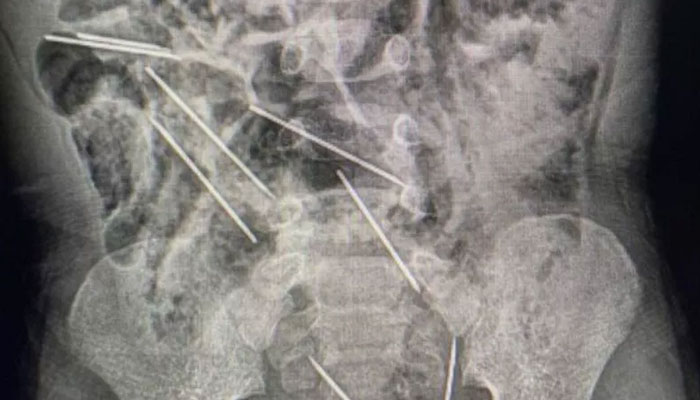

Doctors in northeastern Peru have saved the life of a two-year-old boy who accidentally swallowed eight medical needles while at play.

Upon realising the gravity of the situation, the boy was swiftly transported to Hospital II-2 Tarapoto, where Dr Efrain Salazar led the surgical team. During the procedure, it was discovered that the needles had become lodged in various parts of the boy's abdomen, posing a significant threat to his health.

The release from the San Martin Regional Government disclosed that the needles were found in two locations in the peritoneum on the right side, three on the left side, one in the abdominal wall, and two in a perilous position between the bladder and the rectum.

Fortunately, the surgery was a success, with all eight needles safely removed during a two-hour operation. The medical team also addressed small lesions in the child's small intestine caused by the sharp objects.